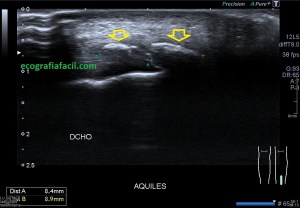

Normalidad, en la imagen 1 y 2 ves un aquiles normal.

1

2

Las imágenes 1 y 2 son la normalidad, es lo que casi nunca solemos ver en este tipo de estudios, pero en ocasiones sí, y como además cuando realizamos este protocolo, siempre es recomendable explorar lado contralateral, podemos muchas veces comparar la región patológica con la normal. El aquiles lo estudiamos siempre en toda su longitud, desde la inserción hasta su origen, en eje corto y en eje largo. Fijándonos bien en toda la ecoestructura posterior de la pierna y estudiando la profundidad de la grasa de Kager.

Las fibras del tendón son alargadas, lineales, tensas con las flexión dorsal.

Ojo con la anisotropía, la hipoecogenicidad producida el ligero cambio de angulación del tendón cuando inserta en el calcáneo posterior…La clave, hiperflexión dorsal, mucho gel y amoldar la posición de la sonda para estudiar estas fibras insercionales.

3

Lo más habitual es encontrar una tendinopatía del tendón, donde vamos a ver un tendón engrosado, hipoecogénico, normalmente a 5 cms de la inserción. Como puedes ver en la imagen 3. Vamos a ver varios grados en función de la afectación del tendón, puede ser global o afectar a fibras profundas o superficiales…siempre recurrir al estudio contralateral.